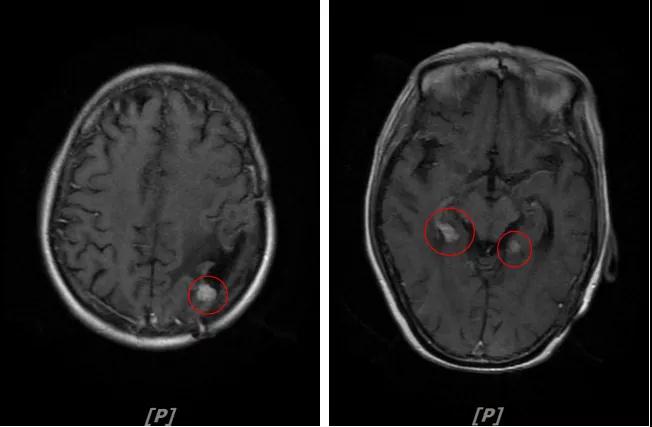

4.病情第3次进展:2018年10月患者头痛症状又加重

头颅增强MR:左侧顶颞叶见片状T1WI低信号、T2WI高信号影,病灶大部信号接近脑脊液;增强后可见左侧额叶、顶叶、两侧海马及右侧小脑半球呈多发斑点状、结节样明显强化,大者大小约14x11mm,较2016-12-11增强老片病灶增大、增多;两侧半卵圆区、侧脑室旁见较对称片状T1WI低信号、T2WI高信号影,增强后未见明显强化( 较2017-8-9MR老片稍明显) ;余脑室、脑池、脑沟大小形态可,中线结构居中无移位。左侧上颌窦粘膜轻度增厚

左顶颞叶转移瘤治疗后改变;脑内多发强化灶,考虑转移,较前增大增多

两侧脑室旁云絮状异常信号:考虑放疗后改变

患者二线治疗的PFS为22个月,2018年11月患者给予后续解救治疗为吡咯替尼(400mg/d)联合阿那曲唑;患者头痛症状好转,病灶继续缩小,继续定期复查。

5. 病情第4次进展:2019年11月患者出现视野模糊等症状

头颅增强MR:左侧顶颞叶见片状T1WI低信号、T2WI高信号影,病灶大部信号接近脑脊液,增强后术区边缘左侧顶叶见结节状强化影,大小约10x8x11mm,较2019-03- 15MR老片大致相仿;右侧脑室三角区见结节样T1WI等低信号、T2WI不均匀稍高信号影,增强后不均匀明显强化,大小约24x18x20mm,较2019-03-15MR老片明显增大;两侧半卵圆区、侧脑室旁见较对称片状T1WI低信号、T2WI高信号影,增强后未见明显强化,较前片相仿;余脑室、脑池、脑沟大小形态可,中线结构向左偏移。

左顶颞叶转移瘤治疗后改变

右侧脑室三角区旁强化结节,较2019-03-15MR老片明显增大 左侧顶叶强化结节,较2019-03-15MR老片大致相仿

两侧脑室旁云絮状异常信号,考虑放疗后改变

患者三线治疗的PFS为14个月,2019年12月给四线治疗为“吡咯替尼+阿那曲唑”基础上联合曲妥珠单抗。

患者视野模糊等症状有所改善,继续定期复查。